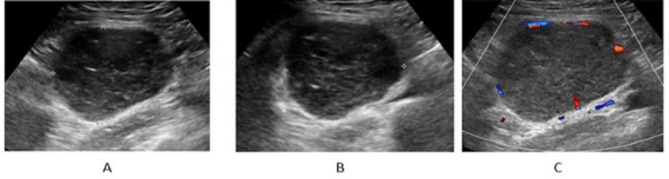

Results: A total of 41 patients were enrolled in the study, comprising 29 with HV-type, 4 with PC-type, and 8 with a mixed type. All patients presented with enlarged lymph nodes (LNs) characterized by a solitary mass, well-defined margins, and increased cortical thickness. Among these, 95.12% (39/41) exhibited an indistinct corticomedullary interface. Additionally, 41.46% (17/41) showed eccentric or asymmetrical cortical thickening, while 58.54% (24/41) demonstrated complete effacement of the fatty hilum. Approximately 24.39% (10/41) of cases exhibited macrocalcification, and 56.10% (23/41) displayed short linear hyperechoic foci within the lymph nodes. Furthermore, patients with HV-type and mixed-type conditions exhibited more abundant blood flow signals compared to those with PC-type (75.86% vs. 25% vs. 87.50%, P = 0.018).

Conclusions: Ultrasound characteristics of UCD generally comprise sizable, solitary masses with clearly delineated borders, a thickened cortex, and disappearance of the fatty hilum. Principal imaging indicators encompass microcalcifications and short linear hyper-echoes. Ultrasound represents an effective and non-invasive modality for the early identification and diagnosis of UCD.